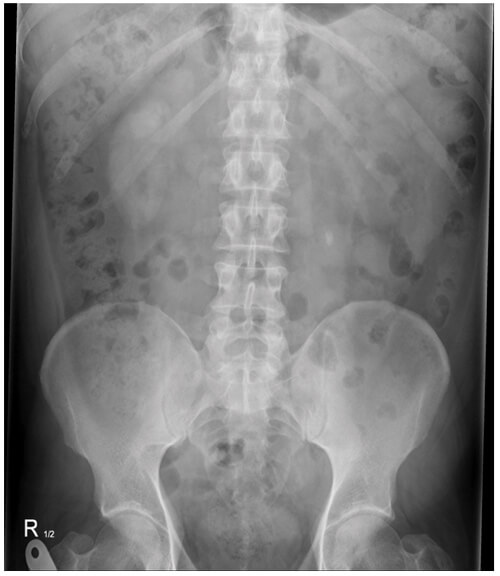

- What does this plain X-ray of kidneys, ureters and bladder (KUB) show?

There is a left upper ureteric stone measuring approximately 8mm in maximal diameter. There is also a smaller left renal stone (around 4mm over the 12th rib).